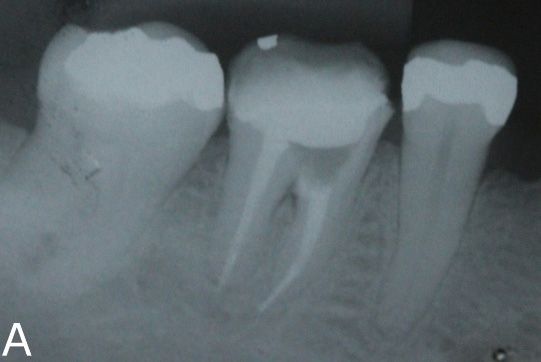

A 42-year-old female patient came to the private practice complaining of spontaneous pain on tooth number 36. According to the patient file, endodontic retreatment had been performed on it. During the clinical exam, the tooth presented positive vertical and horizontal percussion tests. Radiographically it showed a lesion in the furcation region, and endodontic treatment (Figure 1).

Figure 1: Initial x-ray.